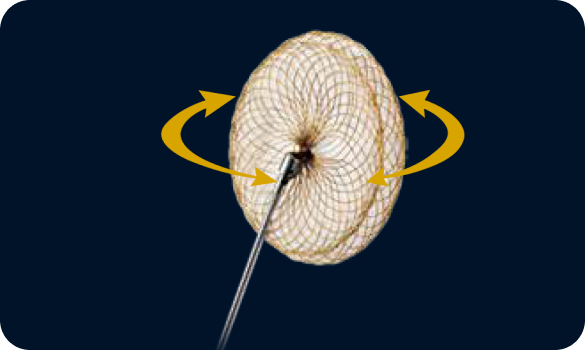

360 flexible rotation, accurate positioning and safe detachment

The CeraFlex™ wire loop connection system offers an accurate final positioning without the adverse tension or stress caused by the delivery cable.